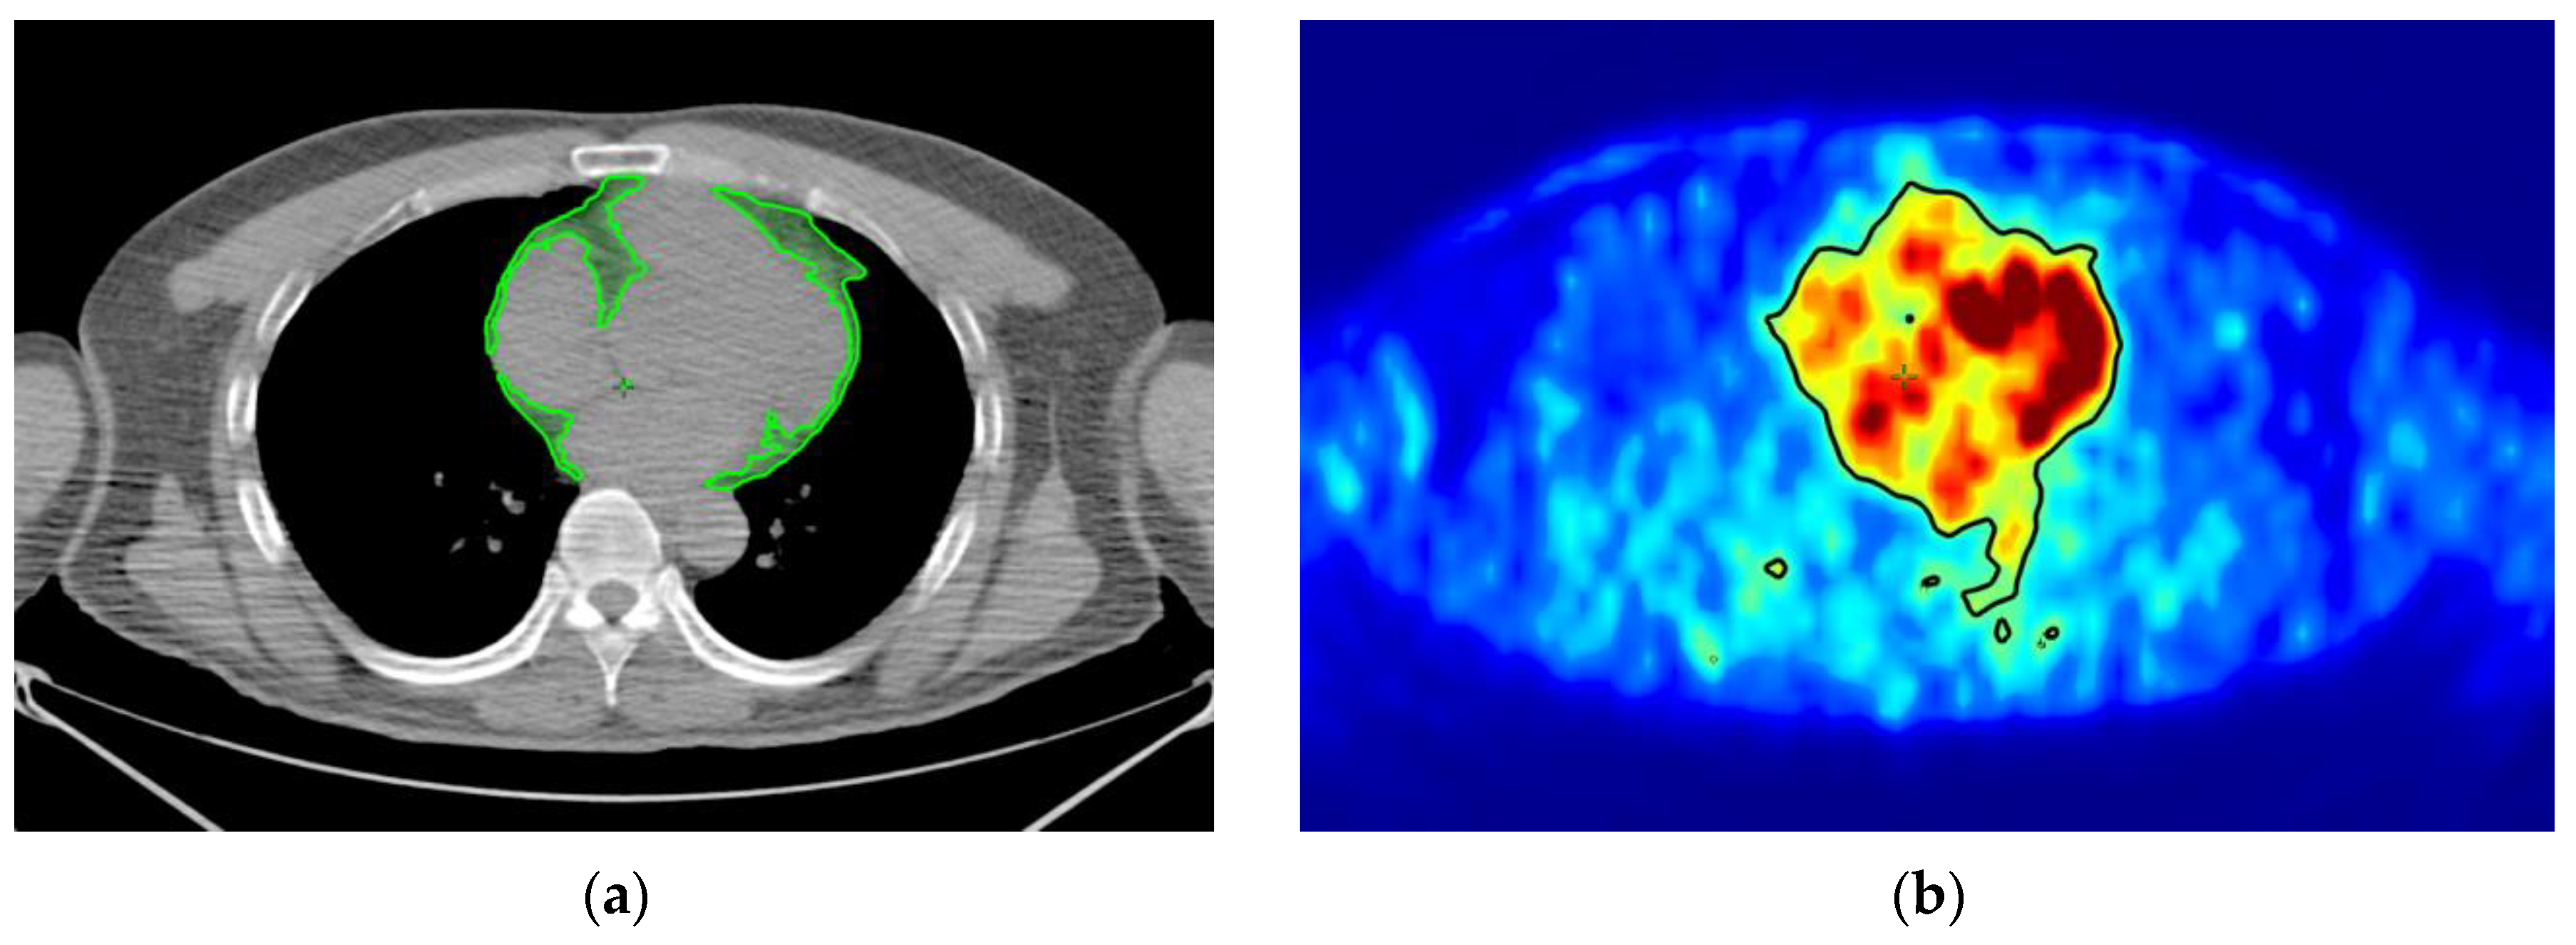

4. Materials and Methods